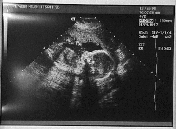

It's never too early to start embarrassing your kid (or kid-to-be). So here are the first baby pics. Years from now, you can say "I remember when you were just 1.9cm long...."

9 weeks, about 1.9cm.